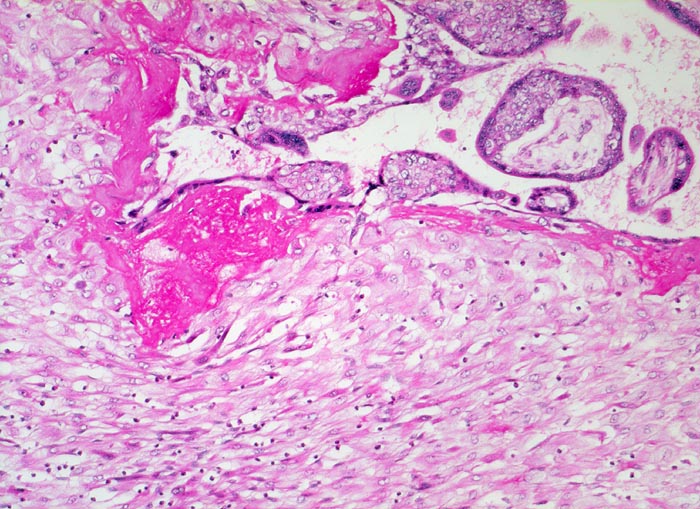

PathoPic ID 5216 - Gravidität: Haftzotten

Gravidität: Haftzotten

Normalbefund

Plazenta

Unten im Bild die hellen zytoplasmareichen Deziduazellen mit vesikulären Kernen.

Fibrinoidschicht an der Deziduaoberfläche.

Kernknospe.

11. Schwangerschaftswoche. Normale Schwangerschaft